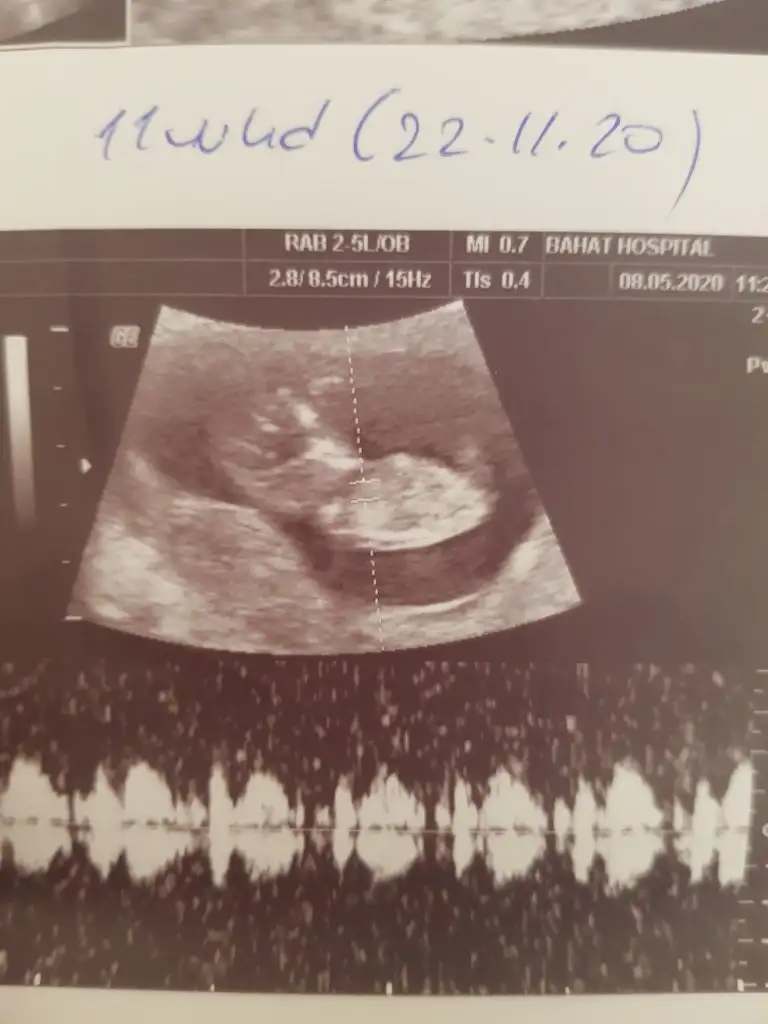

12 haftalik usg resmi bi.kucuk tahmin yokmuuÇok karanlık 11 12 13 haftalarda paylaşabilirsiiz

Meraba bizde 12 haftaligiz bu resimde bizede bi tahminde bulunurmusunuzŞimdiki usg ni atsana canım

Kaç haftalık usg